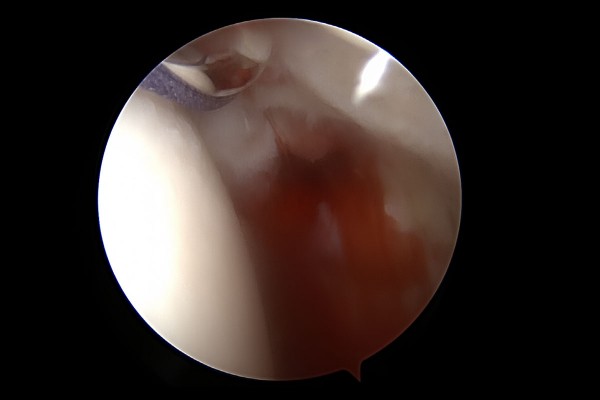

어깨 앞쪽을 최소절개하여, 묶어둔 이두근 장두를 빼냅니다.